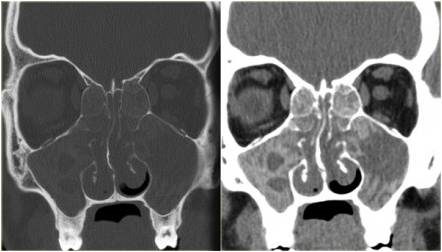

Diagnostyka obrazowa zatok staje się coraz bardziej istotna dla lekarzy dentystów, którzy posiadają w swoich gabinetach aparaty tomografii stożkowej (CBCT). W zależności od wielkości pola obrazowania w CBCT są widoczne fragmenty zatok szczękowych aż po całe zatoki szczękowe, a w badaniach o największym polu obrazowania wszystkie zatoki oboczne nosa, podobnie jak w badaniu medycznej tomografii komputerowej (TK). Z tego względu celem pracy jest przedstawienie najważniejszych zmian patologicznych zatok szczękowych, z którymi może się spotkać lekarz stomatolog, opisując badania tomografii stożkowej (CBCT).